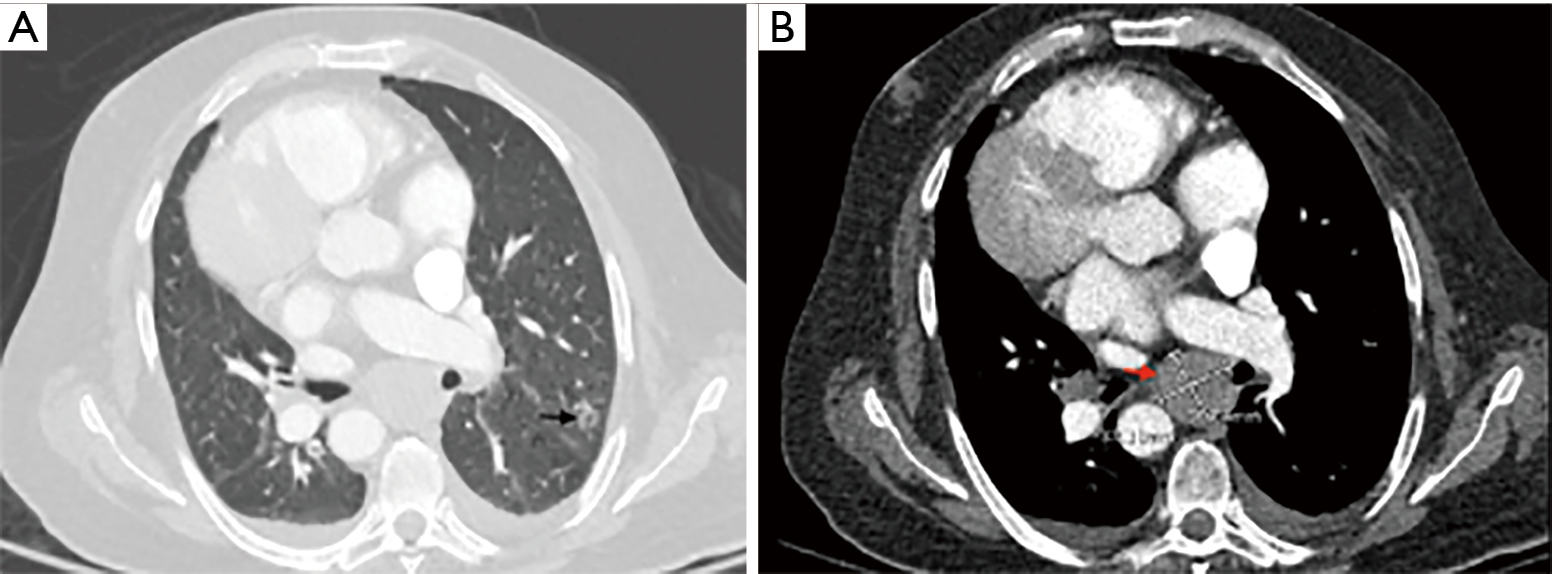

Bronchoscopic Instillation Of DNase To Manage Refractory Lobar

Bronchoscopic instillation of DNase to manage refractory lobar atm.amegroups.com

lung mediastinal lll arrow atelectasis lobar instillation dnase bronchoscopic refractory manage patient cancer nodule significant pulmonary scan chest ct showing